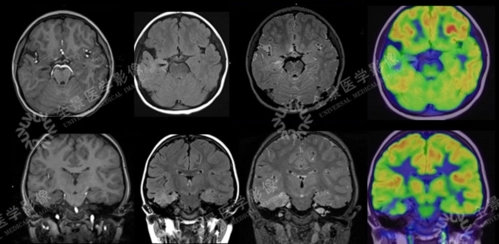

长沙和谐医院癫痫专科特邀癫痫专家湖南省涂秋香教授前来举行会诊今日至28日,癫痫是由脑部神经元异常放电所引起的,癫痫的病因十分的复杂,而且发作症状也是多种多样,这是我们都知道的。癫痫疾病还具有反复发作的特性,我们患者要积极的进行治疗,也要注意做好相关的护理措施来控制癫痫的发作。治疗癫痫病医院专家指出,我们应该对癫痫的发作症状多有了解,做到早发现、早治疗、早控制。那么,癫痫病发作时的症状有哪些?...

长沙和谐医院癫痫专科特邀癫痫专家湖南省涂秋香教授前来举行会诊今日至28日,无论是谁都是不想患有癫痫疾病的,癫痫是一种病因十分复杂的脑部慢性疾病,一旦不幸的患有癫痫,不仅仅是给患者,也会给患者的整个家庭的正常生活造成极大的影响。我们在日常的生活中应该对癫痫的相关病因多有了解,及时的做好预防的工作。那么,癫痫病的病因有哪些?...